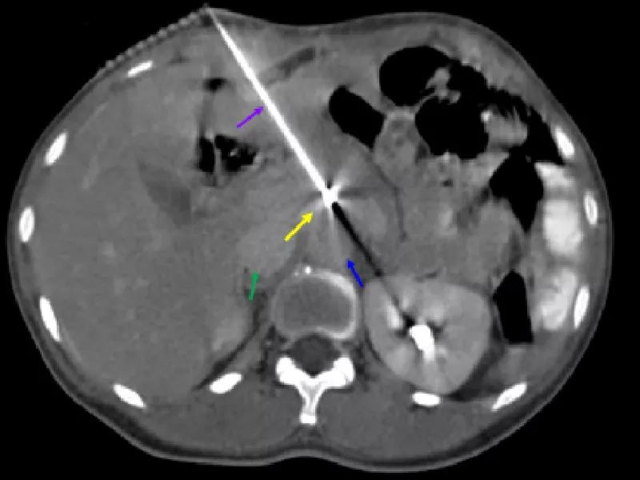

治疗中影像学显示

(黄色箭头为转移淋巴结,红色箭头为肿瘤前方小动脉,绿色箭头为下腔静脉,蓝色箭头为腹主动脉,紫色箭头为插植针)